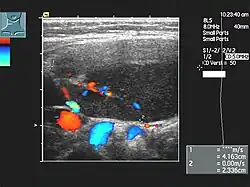

Sonographie des Halses bei hochmalignem Non-Hodgkin-Lymphom der Halslymphknoten (Transversalschnitt mit farbkodierter Duplexsonographie).